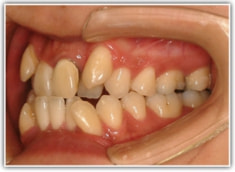

治療前

セファロ分析結果:上顎の劣成長と下顎の過成長が認められる値が出ています。重度の叢生といえます。

骨格的な下顎前突の傾向は強くはありませんが、歯牙の状態によって反対咬合が認められます。LowTongue(低位舌)もあります。

修復歯、補綴歯もあります。下顎8番が水平埋伏しています。